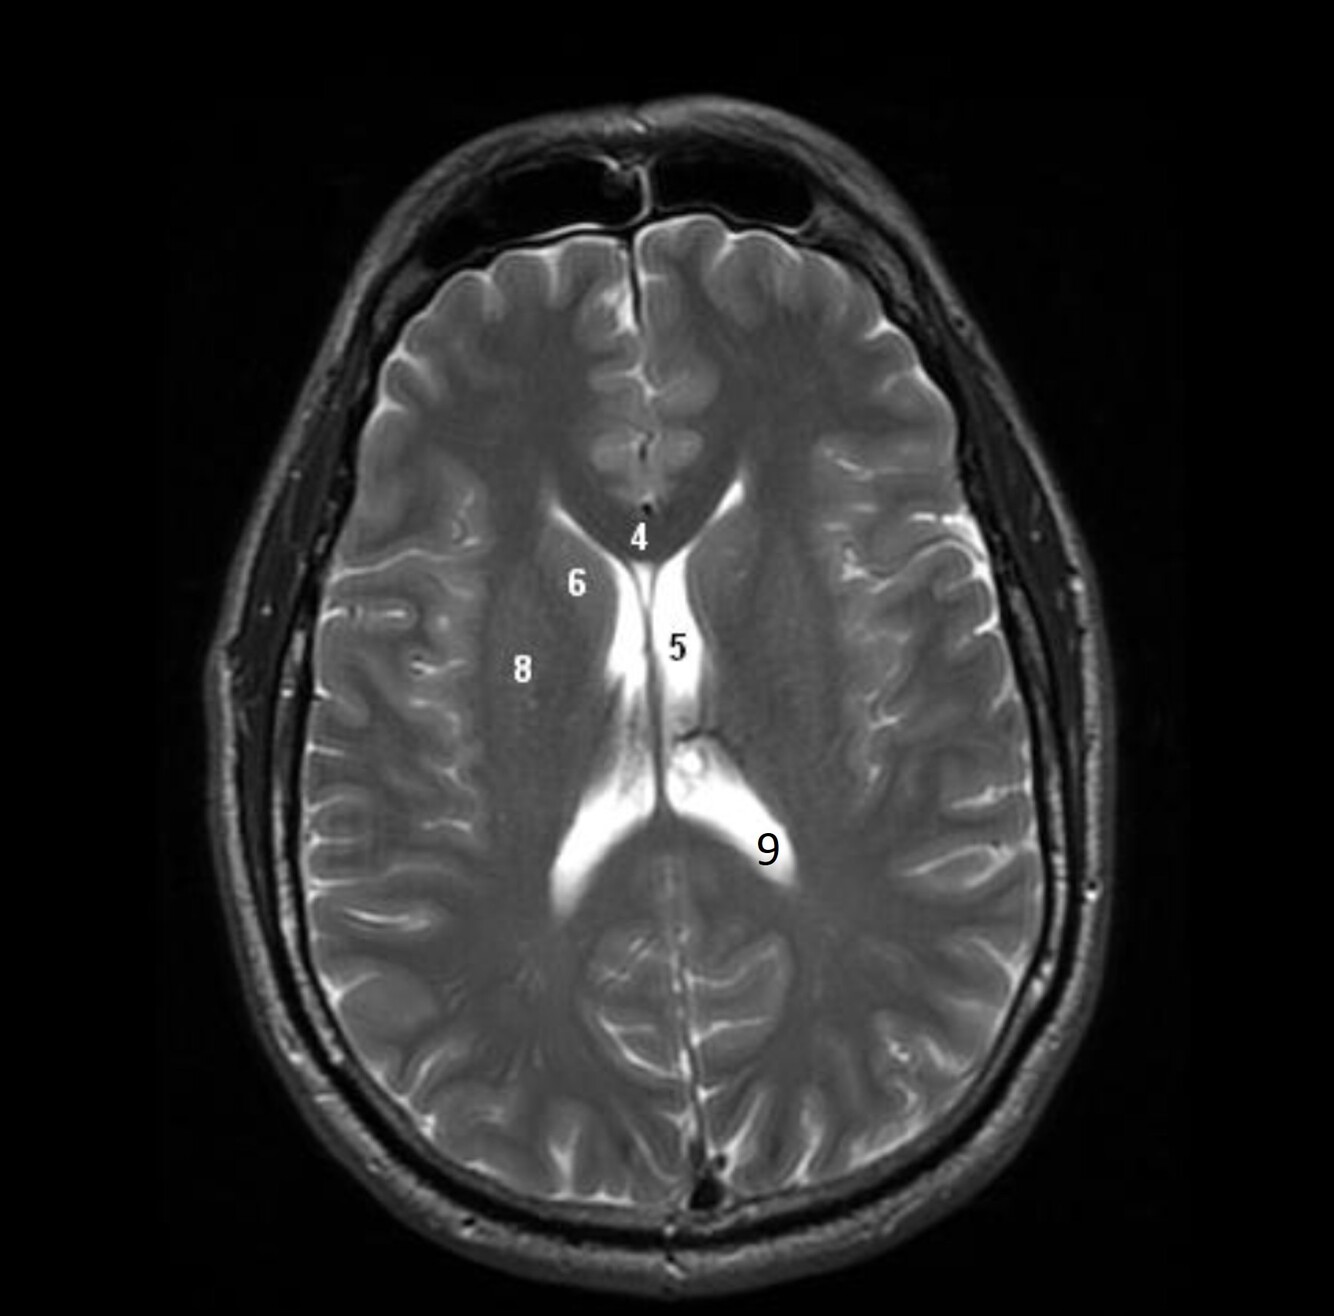

11

Q

Label 4,5,6,8,9

A

4=Genu, CC

5=Lt lateral ventricle (body)

6=Head of Rt caudate nucleus

8-Rt Lentiform nucleus

9=Lt lateral ventricle (post. horn)